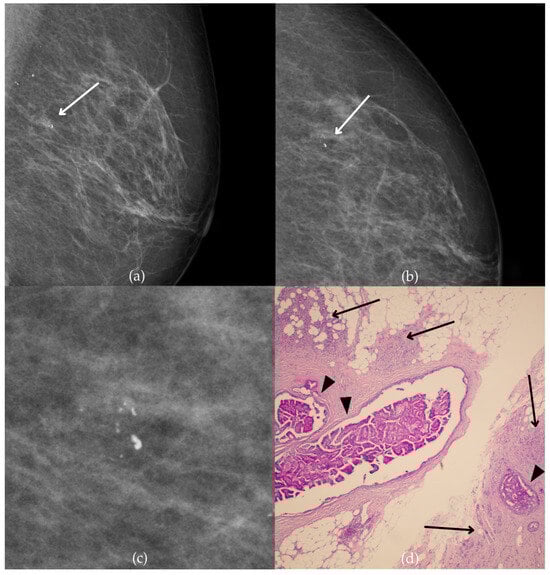

Mammogram and histopathological images (Figure 10) of a 66-year-old patient’s right breast show architectural distortion with associated fine pleomorphic calcifications of segmental distribution in the upper outer quadrant, corresponding to a BI-RADS 3 finding. Tissue analysis obtained through biopsy reported an intraductal papillary lesion without epithelial atypia (category B3). The patient underwent an excisional biopsy (quadrantectomy), and postoperative pathology confirmed the absence of carcinoma. One year after the initial diagnosis, the most recent US follow-up was classified as BI-RADS 2, confirming benign findings.

Intraductal papillary lesion without epithelial atypia. (a) Mediolateral oblique (MLO) view; (b) craniocaudal (CC) view of the right breast showing architectural distortion with associated fine pleomorphic calcifications of segmental distribution (marked with arrows) in the upper outer quadrant. (c) Magnified mammographic image of fine pleomorphic calcifications of segmental distribution. (d) The histopathological image of the biopsy sample shows an intraductal papillary lesion without epithelial atypia (HE staining; 40× magnification).